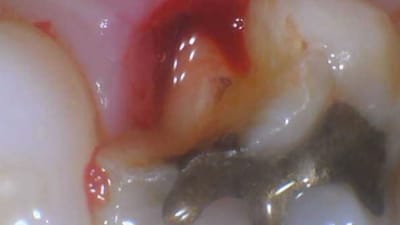

Clinical Briefs Restorative Indirect Materials Treating a Fractured Molar By Daniel Vasquez, DDS November 01, 2023 6 min read